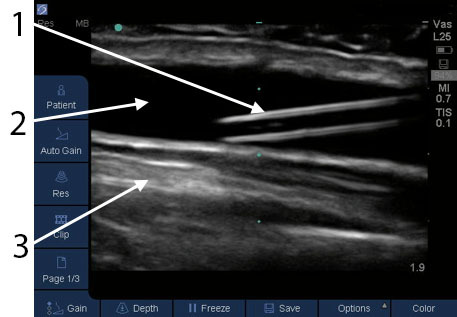

1. Hyperechoic: a substance that sends many sound waves back to the transducer (white)

2. Hypoechoic: a substance that sends few sound wave back to the transducer (grey)

3. Anechoic: a substance that does not send any sound waves back (black)